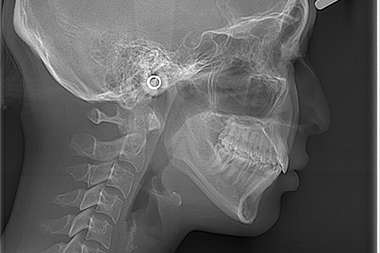

セファロ分析

歯科専用のレントゲンです。矯正治療において分析の根本となるもので、セファロ分析を行うことで口腔内の不正歯列が明らかになります。歯の角度や距離を計測することで、歯の移動の仕方や抜歯の有無などについての判断材料としても有効です。セファロ分析の結果、マウスピース型矯正歯科装置による歯列矯正に向いていない場合もあるので治療を成功させるためにも重要な検査といえます。

セファロ分析により不正歯列を確認

正常な歯列のセファロ分析

正常な歯列

上顎前突のセファロ分析

上顎前突の場合

下顎前突のセファロ分析

下顎前突の場合